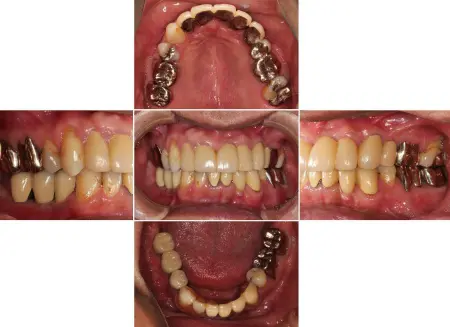

インプラントセラミック

2026.04.0550代男性 欠損していた下左右奥歯にインプラントを埋入してしっかりと噛めるように治療した症例